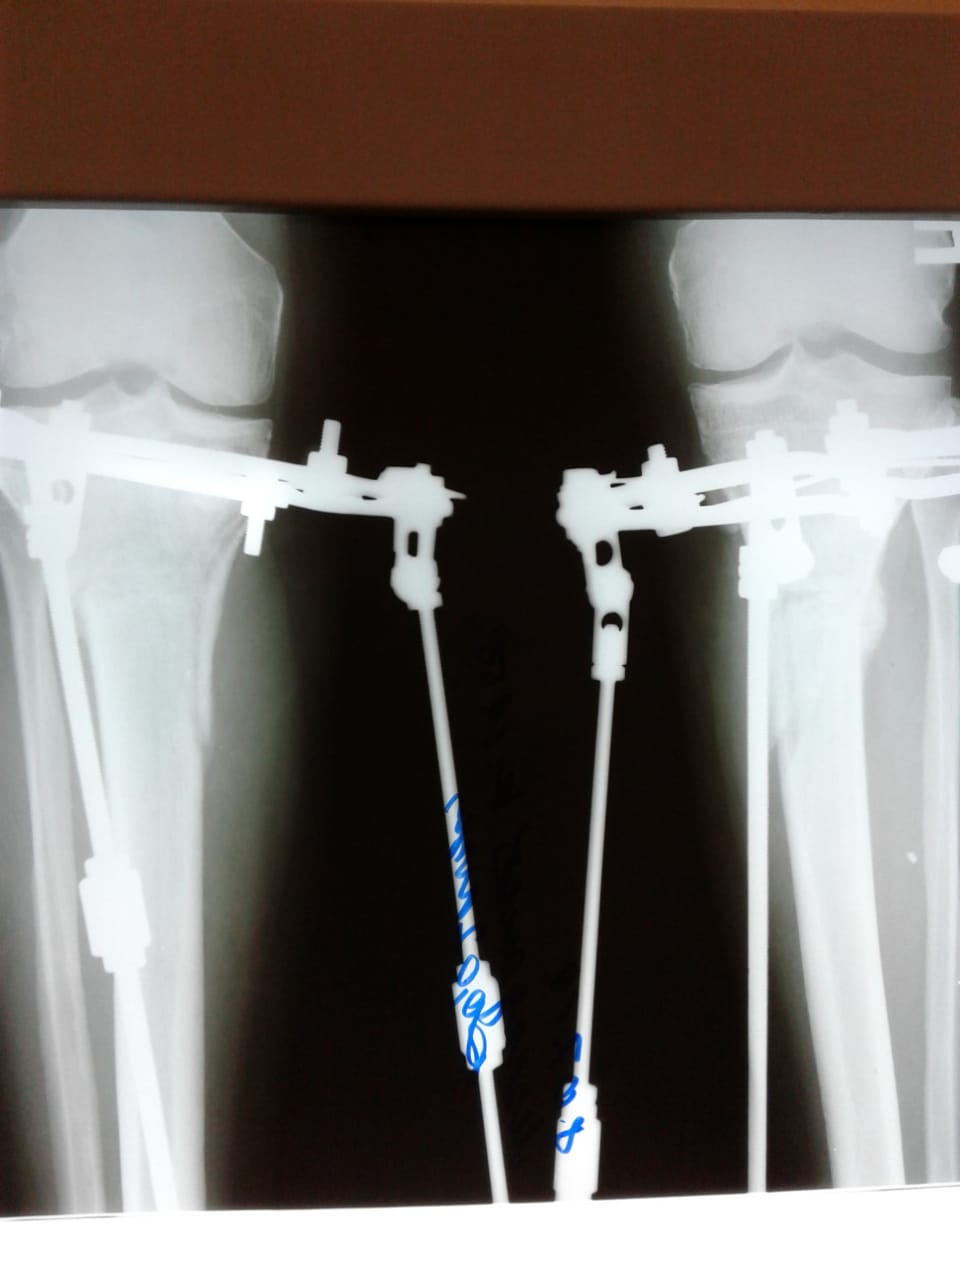

Рентген и фото на фиксации

Вложения

IMG_2964-03-05-19-09-46.JPG

IMG_2963-03-05-19-09-46.JPG